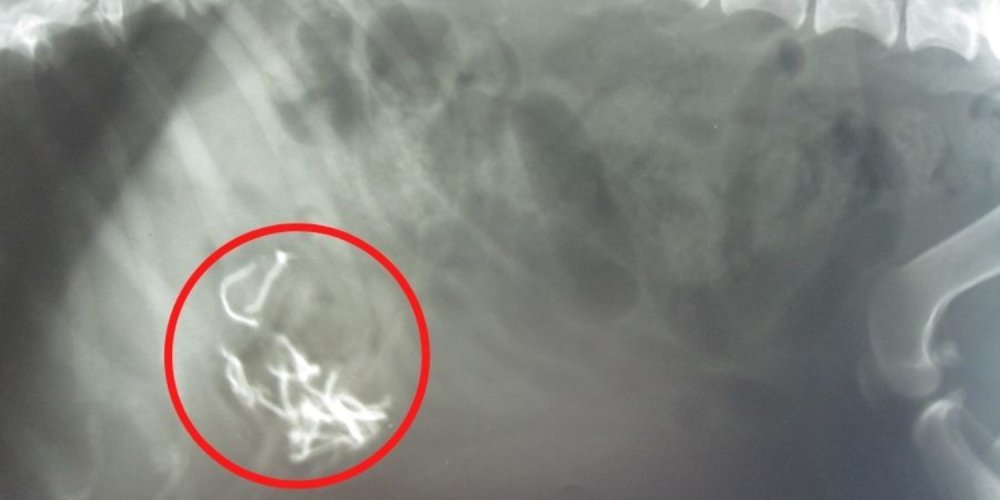

3. Bleščica

Kuža Dexter je bil že v mladosti zelo razigran, tako da je grizel zofe, preproge in bleščice. Nekega večera je njegova družina opazila, da nad kaminom manjka bleščica. Vendar pa Dexter ni kazal znakov bolezni do tistega večera, ko mu je postalo slabo. Naslednje jutro so Dexterja odpeljali v PDSA in rentgenski posnetki so potrdili, da je v njegovem želodcu bleščica. Veterinarji so hitro opravili operacijo in na olajšanje njegovih lastnikov je Dexter prišel domov že za božič.